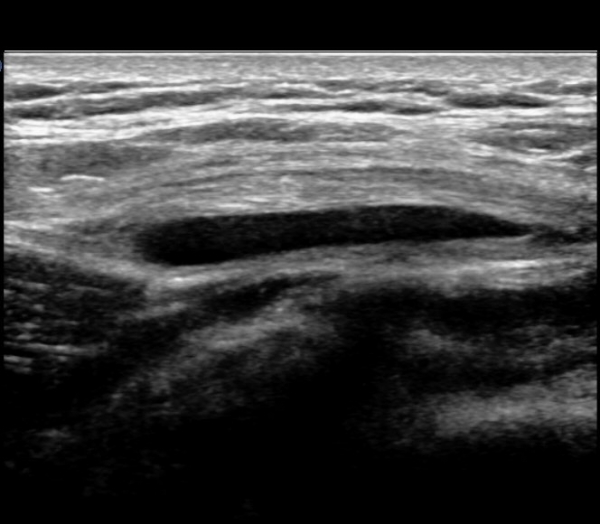

ŽÃËÀÚ¸¦ ¾ÕÂÊÀ¸·Î À̵¿ÇÏ¿© ´ëÀüÀÚ ¾ÕÂÊ È¾´Ü¸é°Ë»ç¿¡¼­ ¼ÒµÐ±ÙÈûÁÙ°ú Àå°æÀÎ´ë »çÀÌ¿¡

¼Ò·®ÀÇ ¼ö¾×Àú·ù°¡ °üÂûµÇ°í(»çÁø 4)

´ëÀüÀÚ ¾ÕÂÊ Á¾´Ü¸é°Ë»ç¿¡¼­ ¼ÒµÐ±ÙÈûÁÙ°ú Àå°æÀÎ´ë »çÀÌ¿¡ ¼ö¾×Àú·ù°¡ ¶Ñ·ÈÈ÷ °üÂûµÈ´Ù(»çÁø 6, 7).